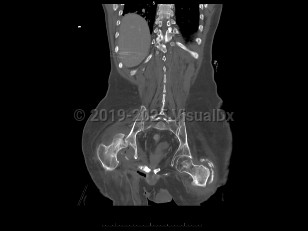

Septic arthritis

Patients present with a swollen, warm, stiff, and painful joint. Fever may be present. The majority of the time, a single joint (usually the knee) is involved. Symptoms develop over 1-2 weeks. If the infection is caused by N gonorrhoeae, patients classically also present with a rash and tenosynovitis. If the infection is due to fungi or mycobacteria, the symptoms may be subtler and may worsen more gradually.

Diagnosis can be made by arthrocentesis. Joint fluid should be sent for analysis including cell count, microscopic analysis for crystals, Gram stain, and bacterial culture. Additional cultures of the joint fluid can be obtained if an atypical pathogen is suspected by history or examination.